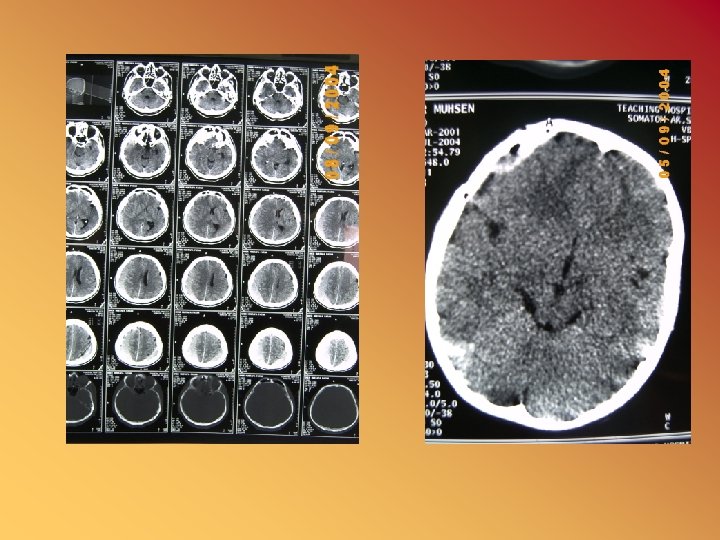

Computed tomography (CT) scanning • A pencil beam of X-ray traverses the patient's head and a diametrically opposed detector measures the extent of its absorption. • Determination of absorption values for multiple small blocks (voxels) • Reconstruction of these areas on a two-dimensional display (pixels) provides the characteristic CT scan appearance

Interpretation of the cranial CT • Ventricular system: size, position, compression • Width of cortical sulci and sylvian fissure: • Skull base and vault: hyperostosis, osteolytic lesion, remodelling, depressed fracture • Multiple lesions: tumor, abscesses, granuloma, infarction, trauma • Abnormal tissue density: – – Midline shift Ventricular compression Obliteration of the basal cisterns, sulci High density( blood, calcification in tumor or AVM or hamertoma) – Low (infarction, tumor, abscess, oedema, encephalitis, resolving hematoma) – Mixed (tumor, abscess, AVM, contusion, hemorrahgic infarct)